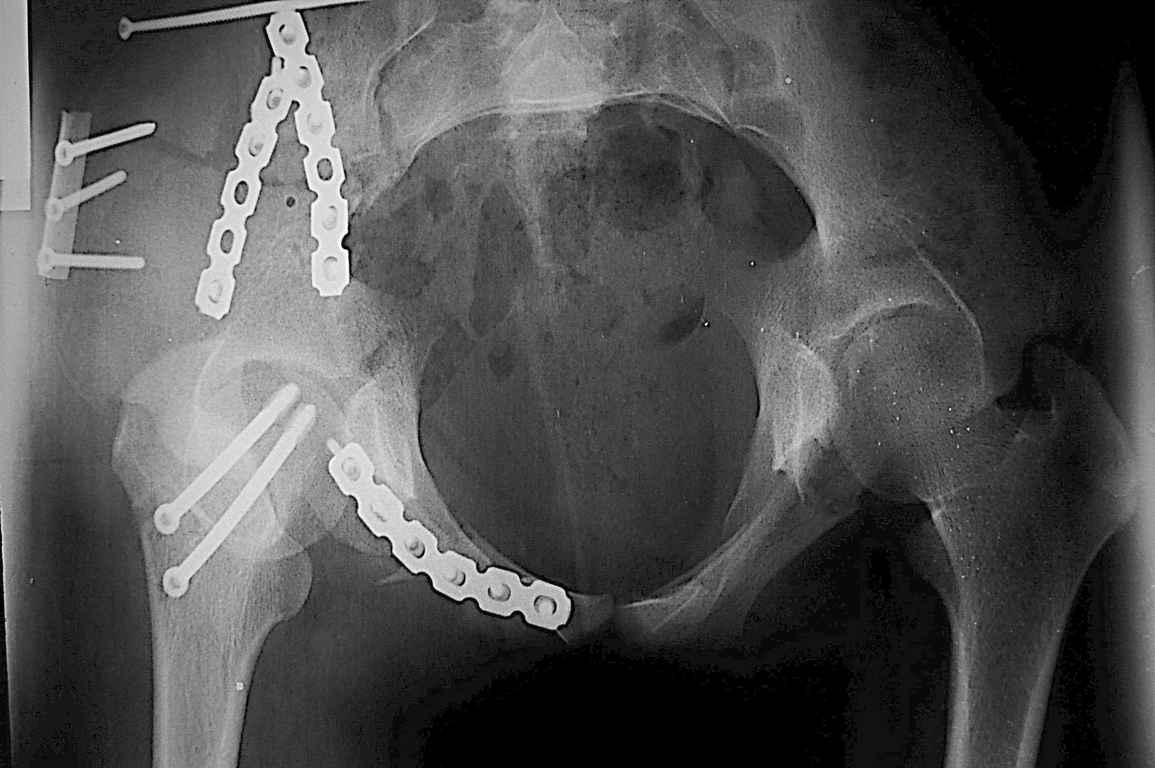

Re: Перелом костей таза

Уважаемые коллеги огромное спасибо за советы! Больная была прооперирована А.В.Рунковым.